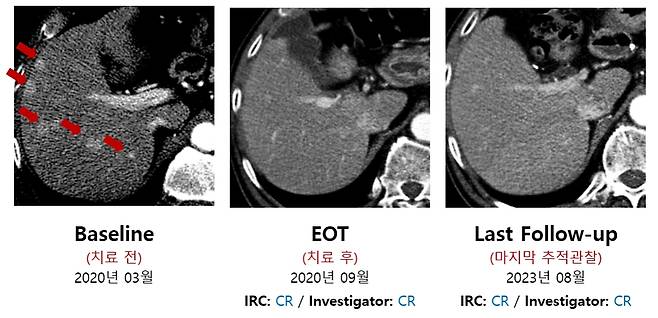

박셀바이오 임상 연구에 참여한 한 환자는 치료 전 여러 개의 암 덩어리가 관찰됐으나, 2020년 9월 치료를 마친 후 더 이상 암이 관찰되지 않아 완전반응(CR) 판정을 받았다. 지난해 8월 마지막 추적관찰 때까지 암이 재발하지 않았다. 이 같은 사실은 독립검토위원회의 분석에서도 재차 확인됐다.